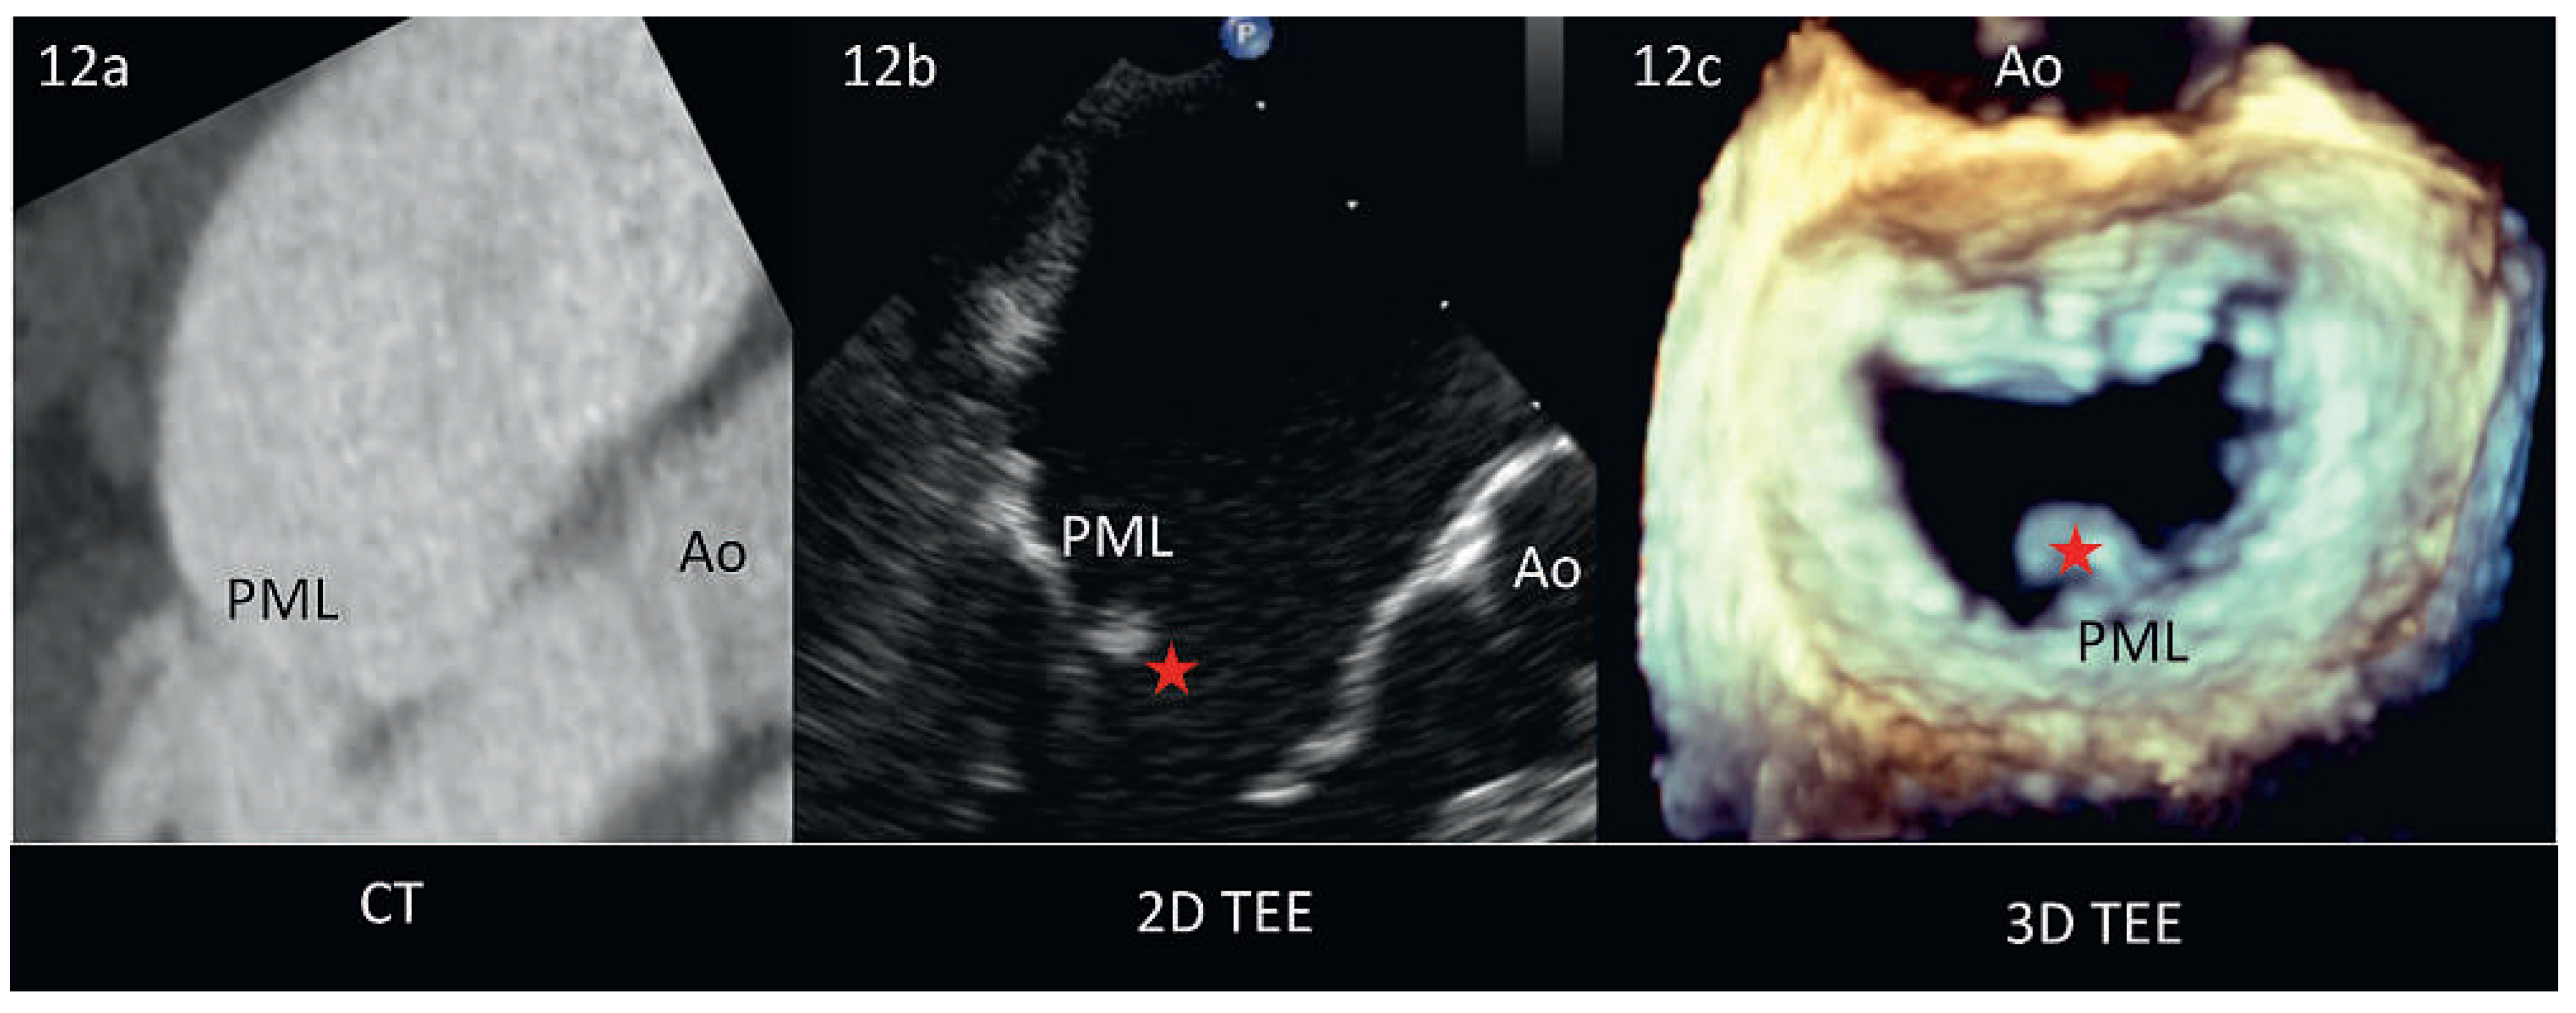

Abbildung 3. Echokardiographische Zeichen der schweren Mitralklappeninsuffizienz. Abb. 3a: 2D-TTE, Parasternale Längsachse, Vena contracta (roter Pfeil). Abb. 3b und 3c: 4–Kammerund 2–Kammerblick, Mitralinsuffizienzfläche (rot) >40% der Fläche des linken Vorhofs (weiss). Der rote Pfeil in 3b demonstriert die Flusskonvergenzzone. Abb. 3d: Entsprechende continous-wave-Doppler Darstellung des Regurgitationsjets: V-förmig und sehr hohe Signaldichte.

Die Farb-Doppler Echokardiographie stellt das wichtigste Instrument zur Quantifizierung der Mitralinsuffizienz dar (Abbildung 3). Es ist darauf zu achten, dass die Aliasing-Geschwindigkeit möglichst hoch ist (60– 70cm/s), um die Fläche des Insuffizienzjets und damit den Schweregrad der Insuffizienz nicht zu überschätzen. Der Schweregrad einer Mitralinsuffizienz wird bei sehr exzentrischen Jets, stark dilatierten Vorhöfen sowie stark eingeschränkter Funktion des linken Ventrikels tendenziell unterschätzt.